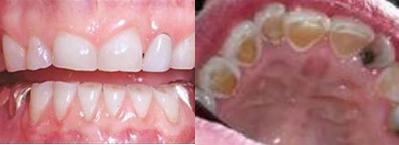

Patients often present with severe attrition of the teeth. This observation is very real for the patient, but convention has it that psychiatric care is needed and any attention to the teeth is only undertaken because of the severe sensitivity which develops from constant vomiting, as in the next photograph.

Please note the severe attrition on the biting edge of the teeth. The erosion on the palatal surfaces is because of vomiting out partly digested acidic food.

Bulimia can cause serious dental problems, and the longer the condition exists, the worst the problem will be. The frequent vomiting that occurs with bulimics can cause the enamel on teeth to wear down over time, resulting in tooth decay, tooth loss, and gum disease. The damage is most obvious on the palatal surfaces of upper teeth, which are affected by the acidic projectile vomiting.